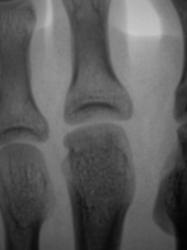

Пациент направлен на исследование стопы врачом хирургом с диагнозом - "Перелом?". Из общения с пациентом возникло сомнение о "наличии травмы". Произведена рентгенография стопы в стандартных проекциях.

При анализе рентгенограммы "данных за перелом" не выявлено. Возникли сомнения по поводу суставной поверхности головки 2 плюсневой кости. ВАШЕ МНЕНИЕ УВАЖАЕМЫЕ КОЛЛЕГИ?

Келлер 2

Я согласен с Вами, и допускаю наличие остеохондропатии, но затрудняюсь с определением стадии.

Действительно, похоже на Келера в стадии исхода.

на остеохондропатию. Болезнь Кёлера2.